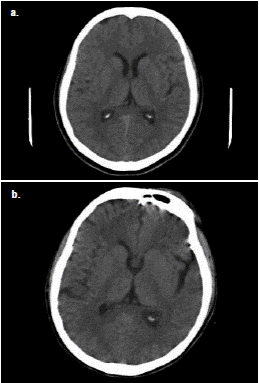

En la valoración psiquiátrica se diagnosticó un episodio psicótico agudo y se inició el tratamiento con lorazepam y risperidona. Los síntomas continuaron con somnolencia, disartria y taquicardia. Se practicaron una tomografía axial (TC) cerebral simple (figura 1) y una resonancia magnética (RM) cerebral simple, cuyas imágenes no mostraron lesiones agudas.

Figura 1 Comparación de las TC simples de cráneo de la paciente del caso 1. a. En la TC realizada en el momento de ingreso al hospital no se observaron alteraciones patológicas. b. Última TC realizada en la institución, en la cual se evidencia aumento de la amplitud de la cisura silviana y de los surcos corticales en forma difusa, con preservación de las estructuras de la línea media (cortesía de Vicente Aljure Reales).